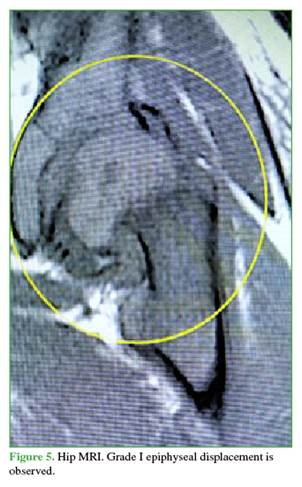

Puncture-aspiration was performed under anesthesia to assess the degree of epiphyseal displacement1 and to evacuate the joint hematoma.2 Then, using a small amount of contrast medium, an arthrogram was performed, which confirmed the displacement and its instability. Magnetic resonance imaging is another modality to reach the diagnosis when instability is suspected; however, an MRI scanner should be available near or within the operating room to perform it during the same anesthetic procedure (Figures 4 and 5).